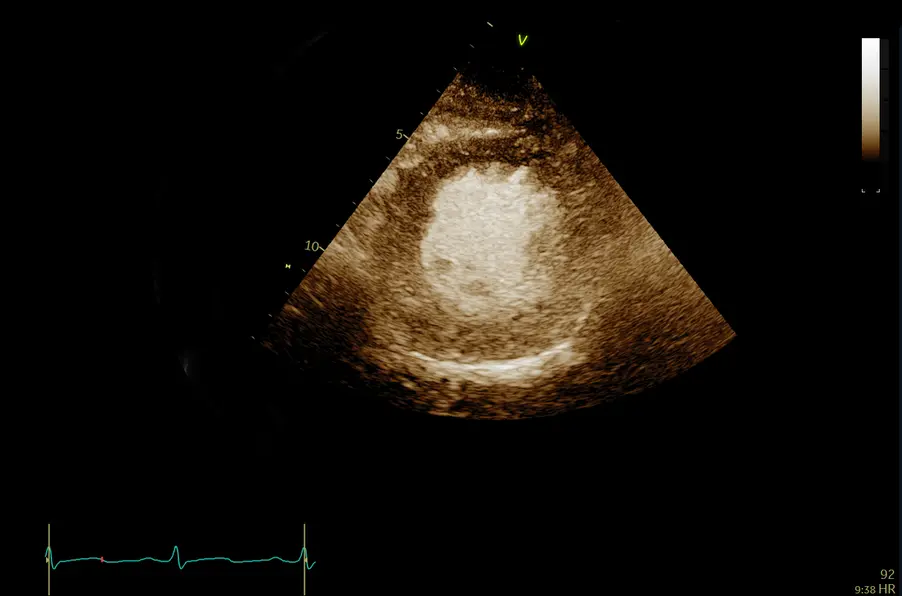

Чреспищеводная эхокардиография

Уверенная визуализация во время инвазивных процедур. TEE датчик 6Tc-RS ультразвуковой системы Vivid T8 совместим с Vivid S6, Vivid S5, Vivid i/q и с Vivid E9 при подключении через адаптер.